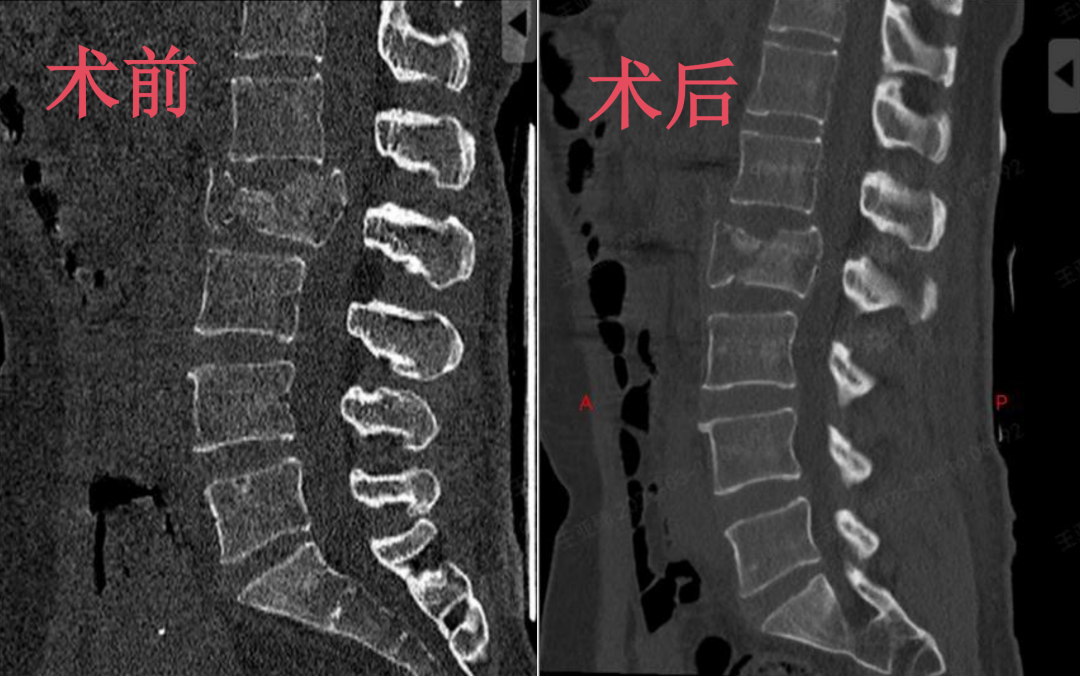

术后复查显示,患者脊柱稳定性成功重建,椎体高度恢复,椎管内侵犯骨块也实现精准复位。